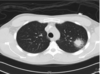

מהו הממצא

קאביטציות- יכולה להיות **סטאפ ארוס אחרי מחלה ויראלית**